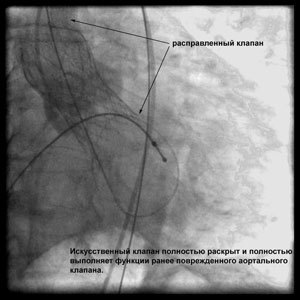

Через прокол (или маленький разрез) в артерии, в сжатом состоянии проводят искусственный клапан, который расширяется при его установке на месте поврежденного аортального клапана. После раскрытия клапан начинает функционировать и восстанавливает полноценную и нормальную работу аорты.

При этом у одного из пациентов ранее были устранены множественные атеросклеротические поражения сосудов сердца «нехирургическим» способом без наркоза. Таким образом, комплексное поражение сосудов сердца и клапана аорты у пациента было вылечено полностью с применением двух высокотехнологических малоинвазивных методик без кардиохирургической операции, требующей наркоза, вскрытия грудной клетки и искусственного кровообращения.